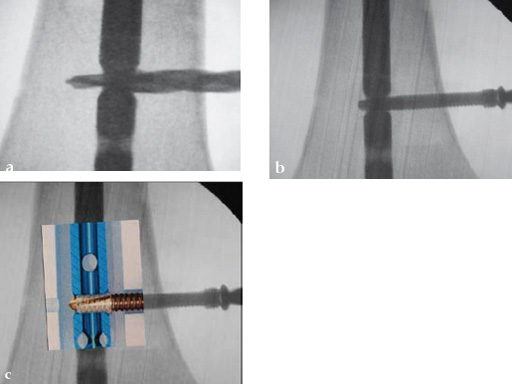

Drilling is identical but the near cortex needs additional reaming so it is wide enough to insert the sleeve. The enlarged hole at the near cortex will be filled by the thicker part which has a larger diameter than the rest of the screw (Fig 2). Use of the hand reamer has proven to be more tactile compared to drilling with machines (Fig 3). Power-driven drilling is only needed for very strong cortices, eg, the femur.

Drilling does not have to be very precise as the ASLS tolerates deviance. An exact amount cannot be given but up to 15 seems to be unproblematic (Fig 4).

To ensure sufficient sized reaming, insert the tip of the reamer until it may touch the hole of the nail. When using the hand reamer, the reamer cannot be damaged.

The sleeve is threaded on the screw by hand just before implantation (Fig 5). The lip of the sleeve needs to face the screw head. The sleeve is positioned correctly when the gold part of the screw is visible on either side of the sleeve (Fig 6). If the sleeve is placed too far on the screw, the connecting bars may be damaged or break. In this case a new sleeve has to be used. A sleeve with broken bars will not work. A sleeve positioner is available which prevents overthreading (Fig 7).

The screw-sleeve construct is pushed into the nail's locking hole by hand. For the final placement, a light hammer (100 gr) may be used (Fig 8). You can actually feel and even hear the correct positioning. Use of a heavier hammer may lead to too deep placement or even pushing the sleeve too far through the locking hole. Control by image intensifier of the reamer and/or screw placement is only needed in the very early part of the learning curve (Fig 9).

The final screw positioning can be felt as the broader screw thread widens the sleeve, filling up the enlarged near cortex.